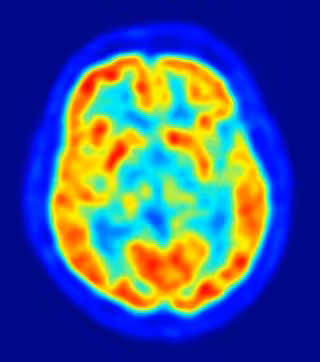

La inhibición de un receptor de azúcares protege contra los efectos negativos de un ictus cerebral

Una investigación en la que ha participado el Consejo Superior de Investigaciones Científicas ha descubierto que el receptor de azúcares lectina MBL juega un papel fundamental en los daños cerebrales asociados al infarto cerebral, con lo que su inhibición podría proteger al cerebro afectado por esta dolencia.